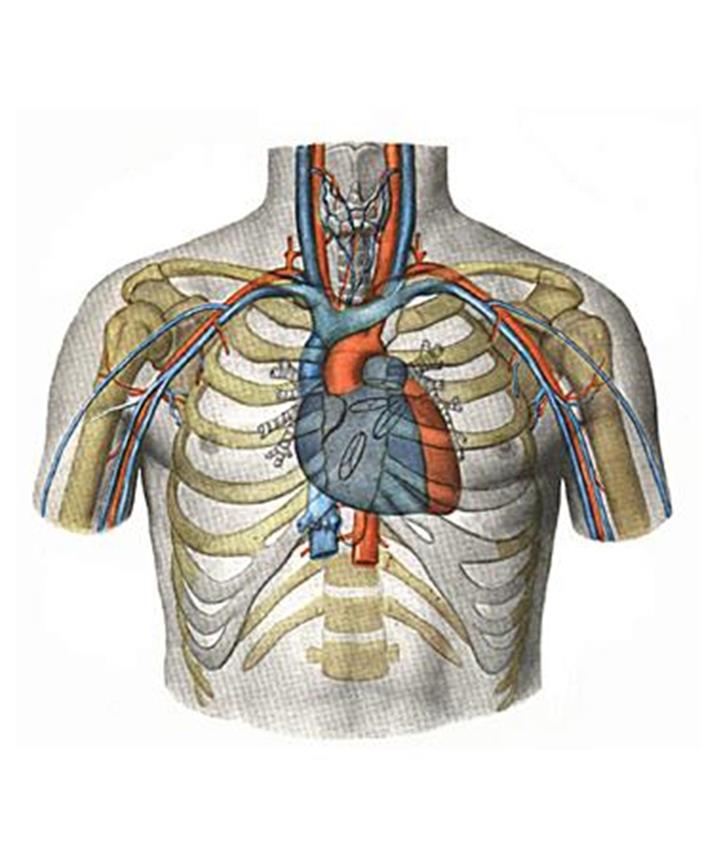

Анатомия Сердца: Расположение и Функции